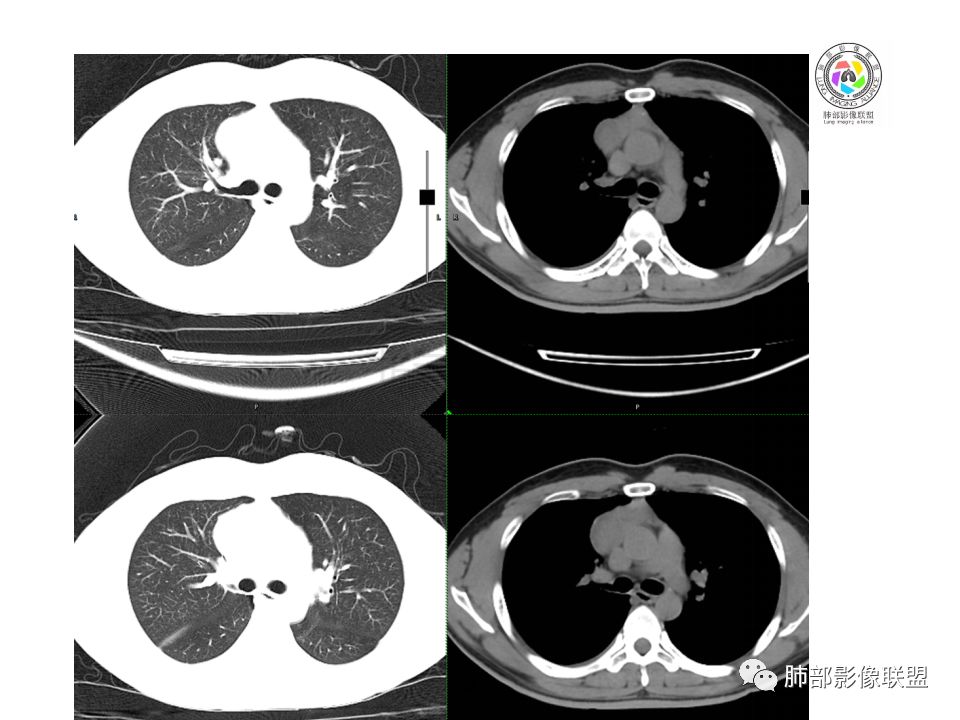

晨读:前纵隔占位,密度不均,沿着右侧纵膈延伸到肺门水平,周围支气管推移,大血管向内推移。临床有重症肌无力,考虑胸腺瘤可能,鉴别淋巴瘤。

患者青年人,前纵隔占位,无增强,猜一个淋巴瘤,不知道右下肺膨胀不全原因是什么

右前纵膈肿块,偏一侧生长,形态欠规则,密度不均匀,其内可见小点状钙化,双肺多发小叶中心结节及钙化灶,右侧胸膜增厚(有陈旧性结核可能),青年男性(27岁),没有增强,考虑,1,前纵隔生殖细胞瘤2,精源细胞瘤

右前上纵隔占位,瘤肺交界面清楚,提示纵隔来源,其内有点状钙化,右侧胸腔积液,有临床症状,年龄轻,考虑生殖来源可能,胸腺瘤待排,请结合临床相关检查或CT增强进一步检查。

前纵隔占位,伴点状钙化;上腔静脉后移位。伴右胸膜局限性增厚,临床有重症肌无力,病人年轻,考虑胸腺瘤可能,鉴别生殖源性肿瘤。

临床症状眼睑下垂,右纵膈占位,偏向一侧,有分叶,跟上腔静脉边界不清,淋巴结肿大,考虑胸腺瘤或胸腺癌

右前纵隔占位,有分隔`低密度、点状钙化,边缘光滑,侵袭心包不明确,伴右胸少量积水,考虑恶性,生殖源性可能大,有视物不清,是否脑转移待查。建议HCG丶AFP检查。鉴别1:胸腺瘤、癌,30一40岁以下,少见,但有眼脸下垂,肌无力,待排除。2:淋巴瘤:侵袭性不强,有点状钙化,不支持。3:畸胎瘤:有低密度丶钙化,建议增强进一步明确。4:神经源性:一般后纵隔常见,不支持。5:LCD:症状少见,可以有树枝状钙化,浆细胞型可以有低密度,增强进一步明确

前纵隔偏侧肿块,病灶内见点状钙化,症状肌无力,考虑恶性,胸腺瘤或神经内分泌癌

没有增强,好像两个病灶,上方三角形的像是胸腺增生。下方肿块,没有增强显得更难了,微钙化,轻度分叶,像有坏死低密度影,右侧少量胸水,胸膜受侵.,有视物模糊眼睑下垂。考虑胸腺瘤B1型及以上、B2型可能或生殖细胞瘤

患者年轻,有肌无力症状,除肿块外,前纵隔密度增高,与心包界限不清,考虑恶性。

前纵隔右区占位性病变,上区与胸腺延续,下区呈分叶状,尽管年龄<30还是首先考虑胸腺瘤,侵袭性可能性大(眼睑下垂不知是否有关)。鉴别主要是生殖细胞类肿瘤,主要是精原细胞瘤。另左肺上叶结核球,右侧胸腔积液,需除外结核性胸膜炎和转移

前纵隔占位性病变,偏向一侧生长,密度不均,可见点状钙化,考虑胸腺瘤,鉴别精原细胞瘤

右前纵隔肿块,边界清楚,密度欠均匀,内似有分隔和低密度区,似有多结节融合,几乎从上到下,年龄较轻,不是胸腺瘤好发年龄,但却有视物模糊,眼睑下垂症状,考虑淋巴瘤?鉴别胸腺瘤?结核?

右前上纵膈肿块,内有点状钙化和少许小片状坏死,局部边界似欠清,右侧胸膜腔少量积液,年轻男性,小于30岁,有重症肌无力,虽然年龄偏轻,仍先考虑胸腺瘤,代排生殖源性肿瘤

晨读前纵隔肿块,偏右侧,密度不均,见点状钙化灶及分隔状低密度影。胸腺瘤>生殖细胞瘤>淋巴瘤

前纵膈占位,上腔静脉受推移,有分叶密度较均匀,结合临床考虑胸腺瘤,待排生殖细泡瘤.淋巴瘤

前中纵隔(胸腺癌区)不规则肿块,密度不均,有坏死区、点状钙化,边缘不会整肿块偏向右侧,向心包流注感,右胸腔少量积水。患者27岁,重症肌无力表现。